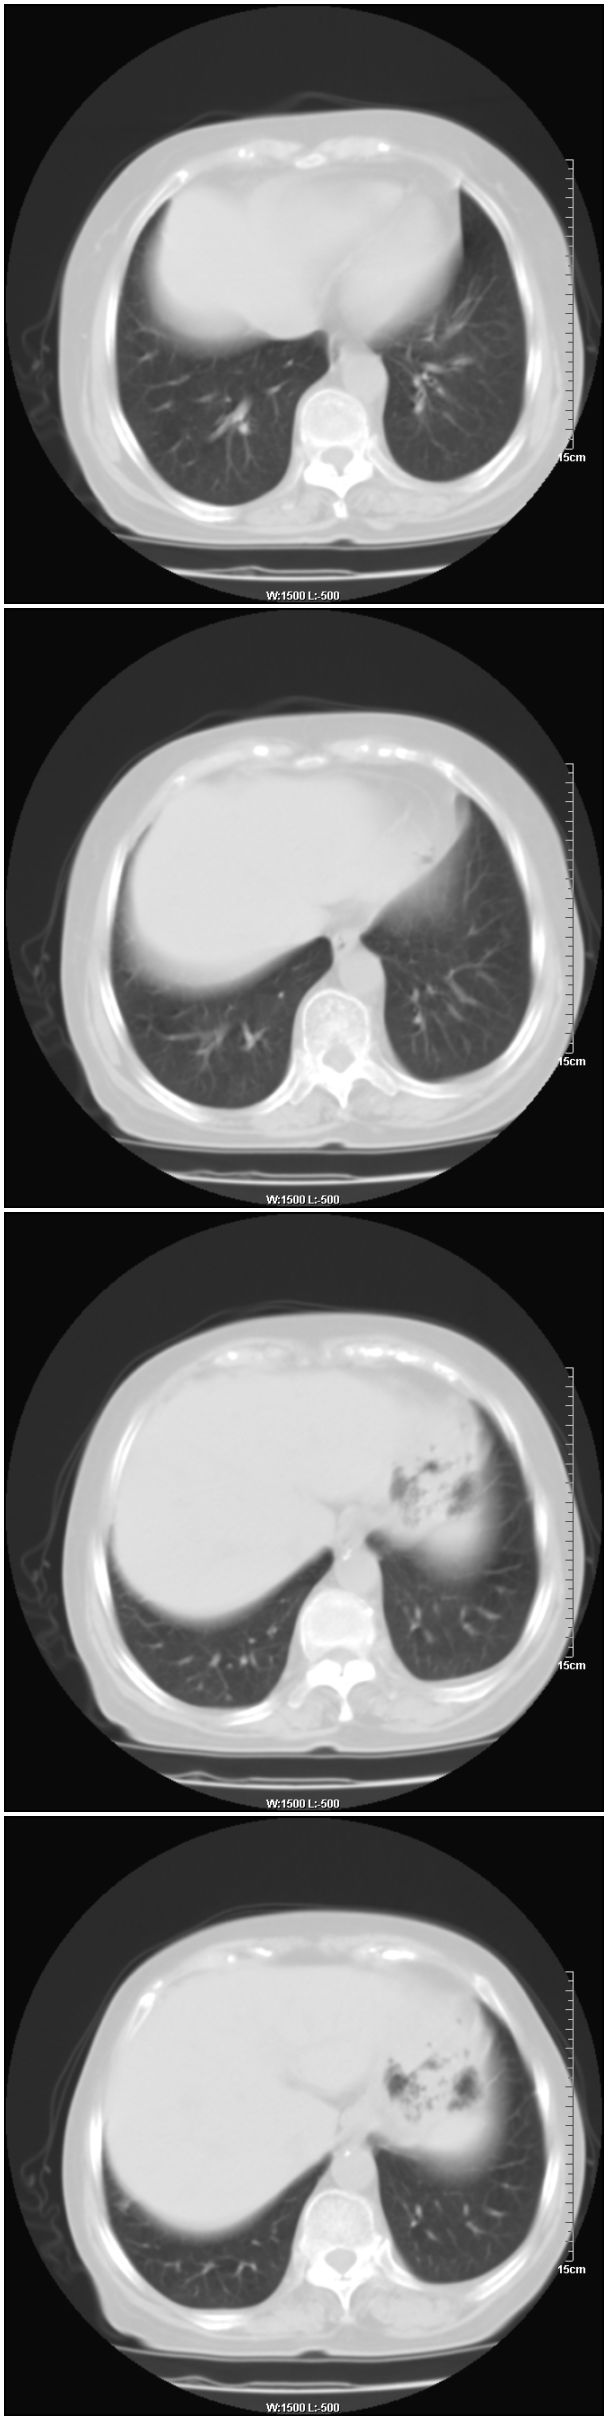

女性,78岁。术前体检发现肺部病变,看看还有什么问题?肺病变是什么性质?

乳腺病变在右侧,右肺门区新生物伴右中叶阻塞性肺炎、部分部张

右肺中叶不规则肿块,管腔阻塞,心包内少量积液,支持右肺中心型肺癌。

1.右侧乳腺病变。

2.右肺病变,考虑:肺癌可能性大。(病变边缘光滑,硬化性血管瘤或其他良性肿瘤待除外)

右侧乳腺内上象限结节影,边缘模糊,右肺病变相邻支气管内见软组织密度影及斑点样钙化灶,考虑肺癌可能性大,建议结合纤支镜检查。

右肺中央型肺癌伴中叶肺不张。